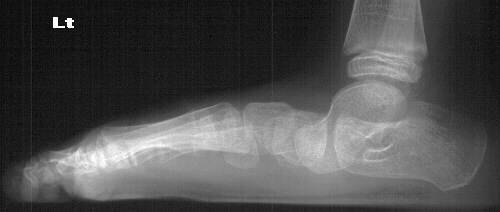

Radiographs reveal the following deformities:

- hindfoot valgus with AP talocalcaneal angle of > 35 degrees

- lateral subluxation/dislocation of the navicular from the talar head

- adduction of the metatarsals with the talus- 1st metatarsal angle to

be divergent medially

- increased lateral talocalcaneal angle with talus plantarflexed on calcaneus

RADIOGRAPHIC FEATURES:

- lateral displacement of the navicular on the head of the talus

- metatarsal adduction

- line drawn through the long axis of the first metatarsal and line drawn

through the long axis of the talus should be parallel or divergent laterally

in the normal foot on AP radiograph

- widening of the talocalcaneal angle on AP radiograph- usually greater

than 35 degrees

- increased lateral talocalcaneal angle with planterflexion of the talus